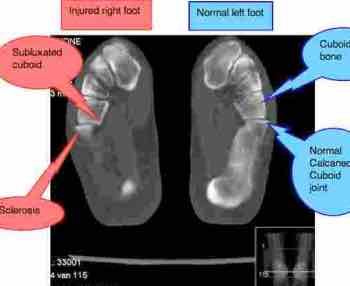

Cuboid subluxation

Talk to your chiropractor about your concerns, and try different options; I hope this contributes. Does he or she also check your foot? Often subluxations of the cuboid or one of the cuneiforms is the problem but it could be in the ankle too.